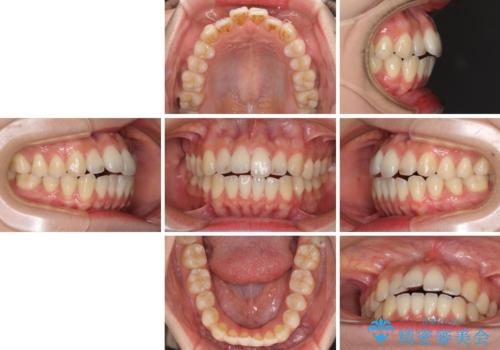

オープンバイトでかみにくい インビザラインによる矯正治療

- 前歯の上下スペースによる食べにくさを気にして来院された患者様です。

インビザラインにより上下の前歯の隙間を閉じていくこととしました。

上下の奥歯を圧下させるようにすることで、前歯を接触させるように計画しました。

上下の隙間に舌が入り込むことがオープンバイトの原因であったため、舌の筋肉のトレーニングも並行して行い、後戻りの抑制を図りました。